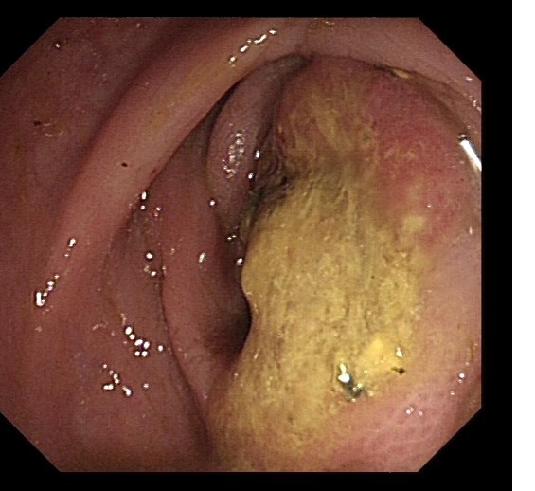

2016-04-19肠镜

【内镜所见】入镜7cm见直肠菜花样肿物,环腔狭窄,不能再入镜,予多点活检。

【内镜诊断】直肠中下段Ca.